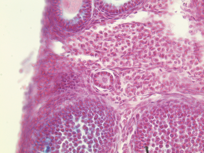

M. Suarez, E. Meinke, V. Romero and Z. Craig, 2026, 'Craig Lab: Mus Musculus Donor APOS001AB Primary Follicles Alcian Blue Slide 1D', https://mother-db.org/MDB0000524, Multispecies Ovary Tissue Histology Electronic Repository, Retrieved: January 15, 2026

Accession #: MDB0000524

Location: follicle

Section thickness: 5 microns

Fixation: Formalde-Fresh Solution

Stain: Light microscopy stain